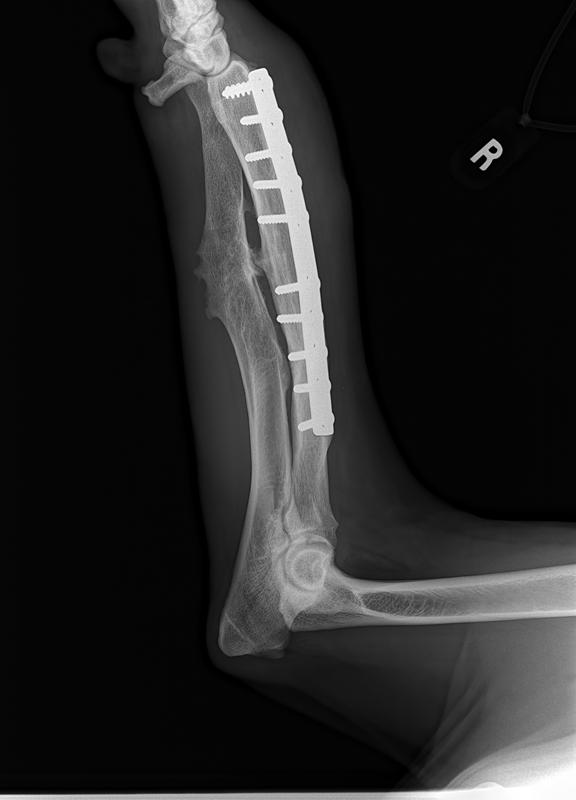

His surgery to remove the implant on his left front leg after a sudden rejection/infection with the plate screws was on September 24th. This is his fourth leg surgery. He had two surgeries on his front legs which were deformed when he first arrived to BHRR and then now he has had to have two more surgeries due to reacting to the Implants.

Surgery started late yet all is done and The Mavie, our true Iron Man has his ‘new’ leg!

BHRR’s Mavie is having that front left leg implant removed. He developed a sudden infection and rejection of the plate/screws.

It does appear that I may well be correct that after 2 years and four months plus from first having the original leg surgery, he is now rejecting this implant. He had this leg first operated on in July 2013. frown emoticon

BHRR’s Mavie, for those who are not familiar with his journey has had two surgeries on his front legs, ended up reacting to the fixator on the left front leg, then last November rejected the implant in the right front leg and now, is having symptoms very similar on the left front leg.

As many are aware, in November of 2014, BHRR’s Maverick, had a violent aggressive reaction to the implant in his right front leg and had to spend several months on strong antibiotics, had to have an emergency surgery to remove the plate/screws and was treated for a terrible abscess from reacting to the implant. His ortho specialist even cultured the implant to see what may be brewing on it…..

How it started with his right leg is how his left leg is now ‘appearing’ to be.